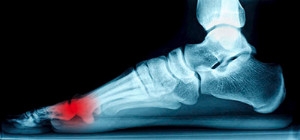

Possible Causes of Gout

The medical condition that is known as gout produces inflamed joints in the big toe and the surrounding area. It can also be referred to as gouty arthritis, and can affect millions of Americans. It occurs as a result of excess uric acid in the bloodstream, and may accumulate for a variety of reasons. These can include genetic factors, having an unhealthy lifestyle, and eating foods that are rich in purines. Some of these foods consist of red meat and shellfish, in addition to excess alcoholic beverages. Drinks that have a high sugar content may also contribute to the onset of gout. The inflammation may be controlled by taking certain medications, in addition to implementing healthy eating habits. If you are afflicted with gout, it is suggested that you seek the counsel of a podiatrist who can help you to manage this condition.

Gout is a type of arthritis caused by a buildup of uric acid in the bloodstream. It often develops in the foot, especially the big toe area, although it can manifest in other parts of the body as well. Gout can make walking and standing very painful and is especially common in diabetics and the obese.

Gout can easily be identified by redness and inflammation of the big toe and the surrounding areas of the foot. Other symptoms include extreme fatigue, joint pain, and running high fevers. Sometimes corticosteroid drugs can be prescribed to treat gout, but the best way to combat this disease is to get more exercise and eat a better diet.

Symptoms of gout are warmth, swelling, discoloration, and tenderness in the affected joint area. The small joint on the big toe is the most common place for a gout attack to occur.